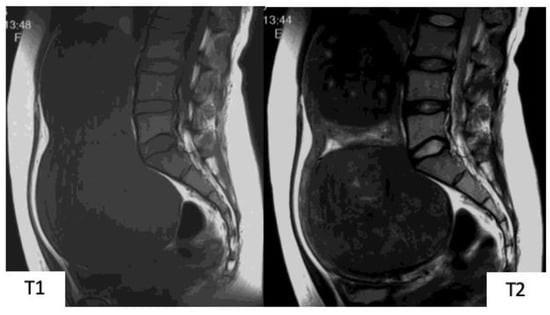

ESS accounts for approximately 20% of uterine sarcomas and is classified as either low-grade (LGESS) or high-grade (HGESS) [6]. LGESS has a high incidence among premenopausal women aged 40–55 years and is characterized by its slow progress; most LGESS are diagnosed when restricted within the uterus (intrauterine) in Stages I and II [7,8]. In pathological images, in many cases, LGESS takes the form of a submucosal or intramural mass with ill-defined edges, which progresses such that it macroscopically appears that the myometrium is being retracted from the endometrium. In some cases, LGESS progresses in a worm-like manner intravascularly [7]. In MR images, the mass exists from the uterine cavity to the myometrium, with a typical presentation in T1WI as low signals and T2WI as heterogeneous high signals. In contrast-enhanced images, LGESS shows moderate and heterogeneous contrast effects. The well-known characteristic LGESS findings in MRI are the “worm-like” findings suggesting that the LGESS is penetrating the normal myometrium while interposing itself intratumorally and images that show worm-like interstitial and extrauterine extensions of multinodular mass [4] (Figure 6 and Figure 7). Diagnosis is simple when typical images are presented. However, in some cases, it is difficult to ascertain infiltrative growth, and due to the fact that LGESS characteristically occurs at younger ages, differentiating between a diagnosis of myoma and adenomyosis is frequently problematic.

Figure 7.

Magnetic resonance images of low-grade endometrial stromal sarcoma. (A): T2-weighted sagittal section, (B): T1-weighted sagittal section, (C): T2-weighted axial section, (D): diffusion-weighted image. Within the uterine posterior wall myometrium, in T2-weighted images, there are relatively high signals, and in T1-weighted images, a mass with ill-defined borders presenting low signals is observed. In (A) and (C), a low-signal band exists in the high-signal mass, presenting a “worm-like” finding that suggests that the low-grade endometrial stromal sarcoma is penetrating the normal myometrium while interposing itself intratumorally. Reduced diffusion is shown in (D).